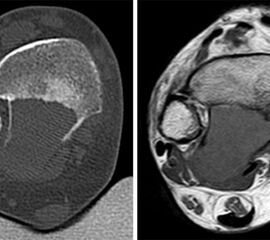

Stellvertretend für gutartige tumoröse Weichteilgeschwulste soll hier die pigmentierte villo-noduläre Synovialitis (PVNS) als wohl häufigste gutartige Weichteilneoplasie des Fußes erörtert werden. Die PVNS nimmt als einzige Entität in allen größeren Studien zu Fußtumoren einen der drei vorderen Plätze ein. Als Synonym der extra-artikulären Form der PVNS ist der Begriff des teno-synovialen Riesenzelltumors gebräuchlich. Die sehnenscheiden- und gelenkkapselreiche Fußanatomie prädestiniert für die Entstehung einer PVNS (Abb. 32). Das weibliche Geschlecht ist doppelt so häufig betroffen, das bevorzugte Alter liegt zwischen 30-50 Jahren. Eine schmerzlose, nur langsam größenprogrediente Schwellung ist das häufigste Symptom. Die Rezidivrate wird mit bis zu 30% angegeben 49. Bei der PVNS handelt sich um einen fibro-histiozytären Tumor (echte Neoplasie) und nicht wie ehemals angenommen um ein inflammatorisches oder posttraumatische Geschehen. Für die intraartikuläre Form, die wiederum in eine noduläre/lokalisierte und diffuse Form unterteilt werden kann, stellt das Sprunggelenk die dritt-häufigste Lokalisation am gesamten Körper dar (Abb. 33).

Im Röntgen zeigt sich gelegentlich eine gut abgrenzbare Weichteilformation (bei nodulärer Form) und knöcherne Druckarrosionen der angrenzenden Knochen. Sekundäre arthrotische Veränderungen der angrenzenden Gelenke sind möglich. Die MRT kann mit einem stark T2-gewichtetem Gradientenecho sog. Suszeptibilitätsartefakte der Hemosiderin­ablagerungen darstellen. Diese führen gewöhnlich zu charakteristischen Signalaus­löschungen in T1 und T2 gewichteten Sequenzen. Eine Kontrastmittel-Aufnahme erfolgt in der Regel diffus und inhomogen. Die Therapie besteht in einer offenen Resektion. Wir raten dringend davon ab, intraartikuläre, lokalisierte Formen der PVNS per Arthroskopie resezieren zu wollen. Dieser Tumor sollte, wenn möglich, marginal und nicht intraläsional reseziert werden. Eine arthroskopische Zerkleinerung mit dem Shaver würde aus einer nodulären Form eine diffuse Form produzieren und die Rezidivwahrscheinlichkeit deutlich steigern. Ebenso ist vor einer Radiosynoviorthese (RSO) bei Vorliegen einer nodulären Variante abzuraten. Bei diesem nuklearmedizinischen Verfahren, welches gewöhnlich Anwendung bei chronisch entzündlichen Gelenkerkrankungen findet, werden Beta-Strahler in Gelenke injiziert. Ein therapeutischer Effekt hat sich bisher nicht nachweisen lassen.